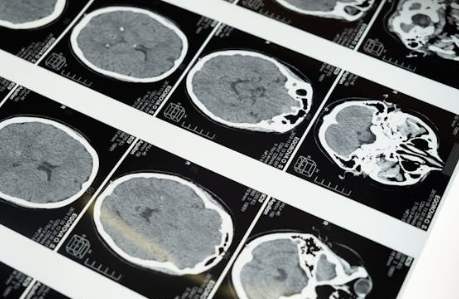

일반적인 MRI나 CT만으로는 진단이 어렵고, 다음과 같은 정밀 검사가 필요해요.

MRI & MRA로 뇌혈관 상태를 전체적으로 파악하고, 뇌혈관 조영술로 ‘연기처럼 피어나는 혈관’ 모양을 확인하며 SPECT 검사를 통해 뇌혈류 흐름을 측정해 수술 여부를 결정하게 됩니다.